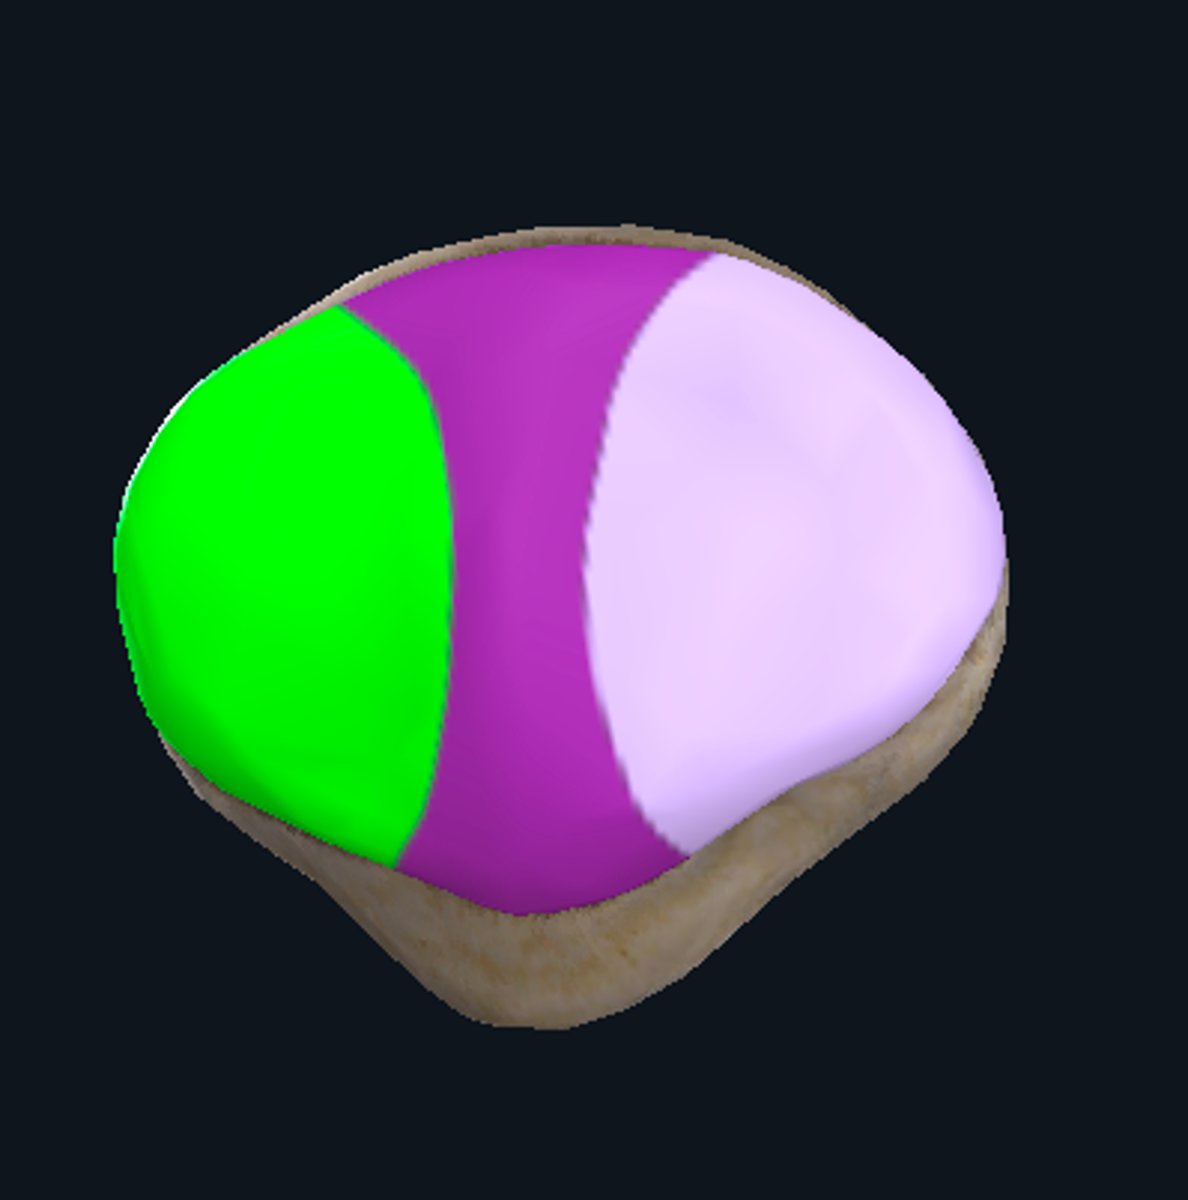

Medial articular surface (for medial condyle of femur; smaller)

green

Lateral articular surface (for lateral condyle of femur; bigger)

green